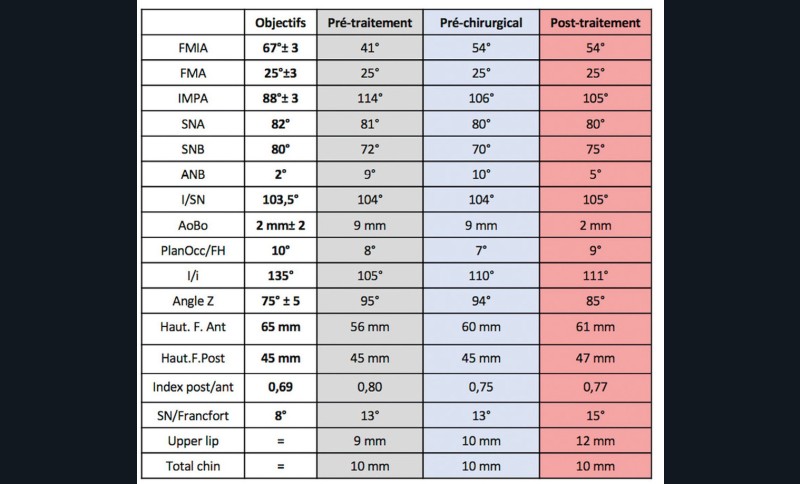

À la vue de l’examen radiographique, elle est au stade CS6 d’après la méthode de maturation vertébrale de Baccetti [1]. Elle présente une classe II squelettique de Ballard par rétrognathie mandibulaire avec un ANB de 9° et un AoBo de 9 mm sur un schéma facial normo-divergent. L’incisive mandibulaire est vestibulo-versée (IMPA = 114°). Le maxillaire est bien positionné. Elle présente de plus une dysharmonie dento-dentaire (DDD) antérieure par excès mandibulaire.

Le traitement de compromis n’étant pas une option chez cette patiente de 16 ans, nous proposons de réaliser un traitement orthodontico-chirurgical avec ostéotomie d’avancée mandibulaire après repositionnement de l’incisive inférieure.

Nous avons pu repositionner l’incisive mandibulaire de 8° (fig. 10), obtenir un surplomb correspondant à la classe II d’Angle et ainsi réaliser l’avancée mandibulaire. Le chirurgien accompagne celle-ci d’une génioplastie afin d’harmoniser le profil. Nous corrigeons la DDD par stripping des incisives mandibulaires ce qui permet de corriger encore de 1° l’axe incisif.

À propos du cas, on note la persistance d’une petite classe II squelettique (ANB = 5°). Cependant, l’axe de l’incisive maxillaire ne permet pas une correction plus importante de la classe II par avancée mandibulaire car le surplomb est déjà faible et l’incisive maxillaire est légèrement versée (106°). Les axes de 11 et 12 auraient pu être améliorés.